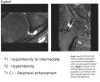

Hip joint의 Paralabral cyst

1. Hyperintense cyst adjacent to labrum

2. Communicates with labral tear

3. Anterosuperior -> posterosuperior -> inferior

4. Associated with impingement

5. ±Septated + lobulated